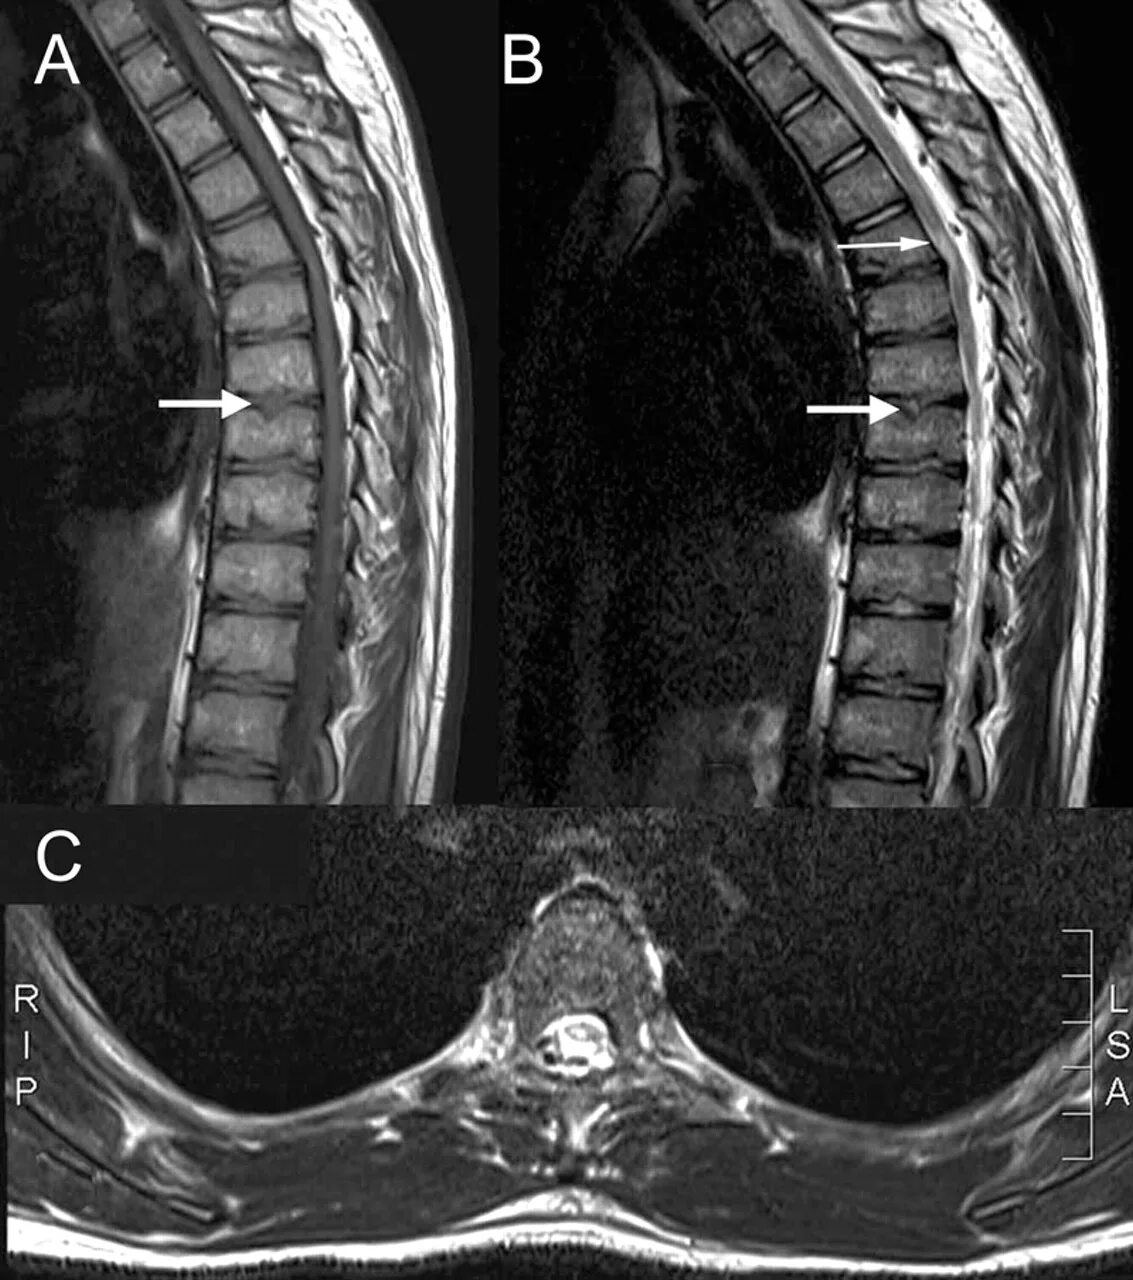

Как выглядит грыжа позвоночника на мрт